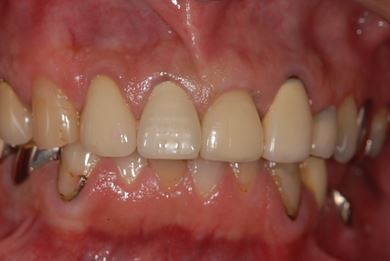

性別/年齢 男性 / 53歳

主訴 インプラント治療相談。

治療方針 骨再生法にて、インプラント治療を可能にする。

治療内容 インプラント2本(GBR)、ハイブリッドセラミッククラウン2本

総治療費 665,963円

治療期間 9ヶ月

治療後